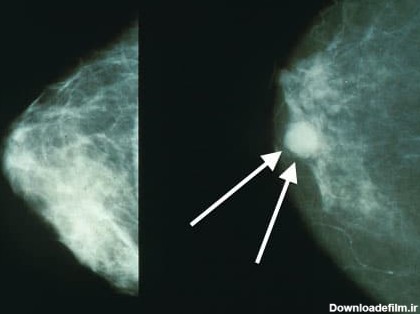

پستان نگاری یا ماموگرافی (Mammography) گونهای روش پرتونگاری است که در علوم تصویربرداری پزشکی

ماموگرافی، تصویربرادی از سینه و از مهمترین ارکان تشخیص سرطان سینه یا هر بیماری سینه است. این سرطان بین خانمها شایع است و باید مرتب سلامت سینه را چک کرد.

عکس ماموگرافی سالم ؛ماموگرافی یک فیلم اشعه ایکس پستان است که بادوز پایین برای تشخیص ناهنجاریهایی درپستان که خیلی کوچک هستند.